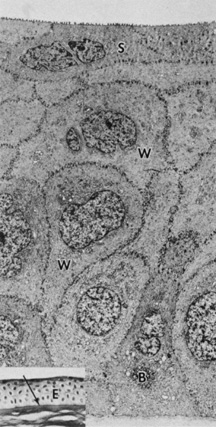

The corneal epithelium is the anterior-most cell layer of the cornea (Fig. 1). It is typically several cell layers thick, consisting of the apical cell squamous layer, the multilayered, polygonal-shaped wing cells beneath the apical layer, and the posterior-most layer of basal cells (Fig. 2). The wing cell layer is two or three cells thick in the central cornea, but tends to be four to five cells thick in the periphery. In total, the epithelium is approximately 50 μm thick in the central human cornea.

Fig. 2. Full-thickness electron micrograph of corneal epithelium. Note the cell shape change with depth, the variation of cell membrane interdigitation, and the intracellular differences between cell types. S, apical surface cells; W, wing cells; and B, basal cells. Also note the microvilli seen along the apical membrane of the surface cells (3,620×). Inset: Epithelium (E) overlies a thin, dense basement membrane (arrow) with no discernible laminar appearance (periodic acid-Schiff [PAS] stain, 330×). (Courtesy of Drs. Rodrigues, Waring, Hackett, and Donohoo.)